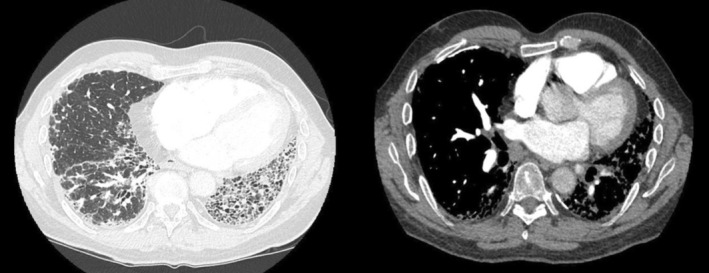

石棉沉滞症是一种因吸入过量石棉纤维而引起的纤维化间质性肺病。我们描述了一位在20世纪70年代和80年代作为理发师工作时因职业暴露而患上石棉沉滞症的患者。没有意识到这一职业是发展石棉沉滞的一个危险因素,导致了一些无效的治疗策略,最终导致了肺移植的需要。最近政府政策的变化有效地减少了这种暴露风险的发生率;然而,鉴于疾病的长潜伏期,我们强调广泛的职业史,包括潜在的历史暴露,仍然是评估间质性肺病的重要组成部分。我们还概述了第二波石棉相关肺部疾病的许多原因,这些疾病现在才出现,并鼓励临床医生继续在未分化的纤维化肺部疾病的鉴别诊断中维持石棉沉滞。

Asbestosis is a form of fibrotic interstitial lung disease caused by the inhalation of excessive asbestos fibres. We describe a patient who developed asbestosis due to occupational exposures while working as a hairdresser in the 1970s and 1980s. Not appreciating this profession as a risk factor for developing asbestosis led to several treatment strategies that were ineffective and eventually led to the need for lung transplantation. More recent changes to governmental policy have effectively reduced the incidence of such an exposure risk; however, given the long latency of the disease, we emphasise that a broad occupational history including potential historic exposures remains an important component of the assessment of interstitial lung disease. We also outline many reasons for a second wave of asbestosis-related lung disease that is only now emerging and encourage clinicians to continue to maintain asbestosis on the differential for working up undifferentiated fibrotic lung disease.